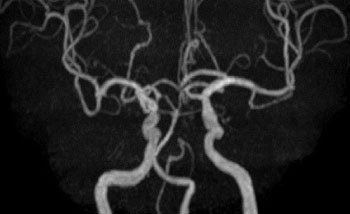

脳血管画像(MRA)

頸動脈の血栓(プラーク)

脳ドック

脳血管疾患の多くは何の前触れも無く起こり、発症してからの治療では重い後遺症が残ることも少なくありません。脳ドックでは、脳と脳・頚部血管の病気の早期発見と予防を目指して各種検査を行います。

脳ドックでわかること

まだ症状の出ていない脳の病気や脳血管の病気を発見することができます。

1. 脳梗塞

2. 未破裂脳動脈瘤

3. 無症候性脳梗塞

4. 脳・頚部血管の閉塞・狭窄

5. 脳卒中の危険因子

検査内容

• 問診・診察・身体測定・血圧測定

• 血液検査(GOT、GPT、γ-GTP、中性脂肪、HDLコレステロール、LDLコレステロール、空腹時血糖、HbA1c)

• 尿検査(糖、蛋白)

• 心電図

• MRI(磁気共鳴断層撮影)

• MRA(磁気共鳴脳血管撮影、頸部含む)